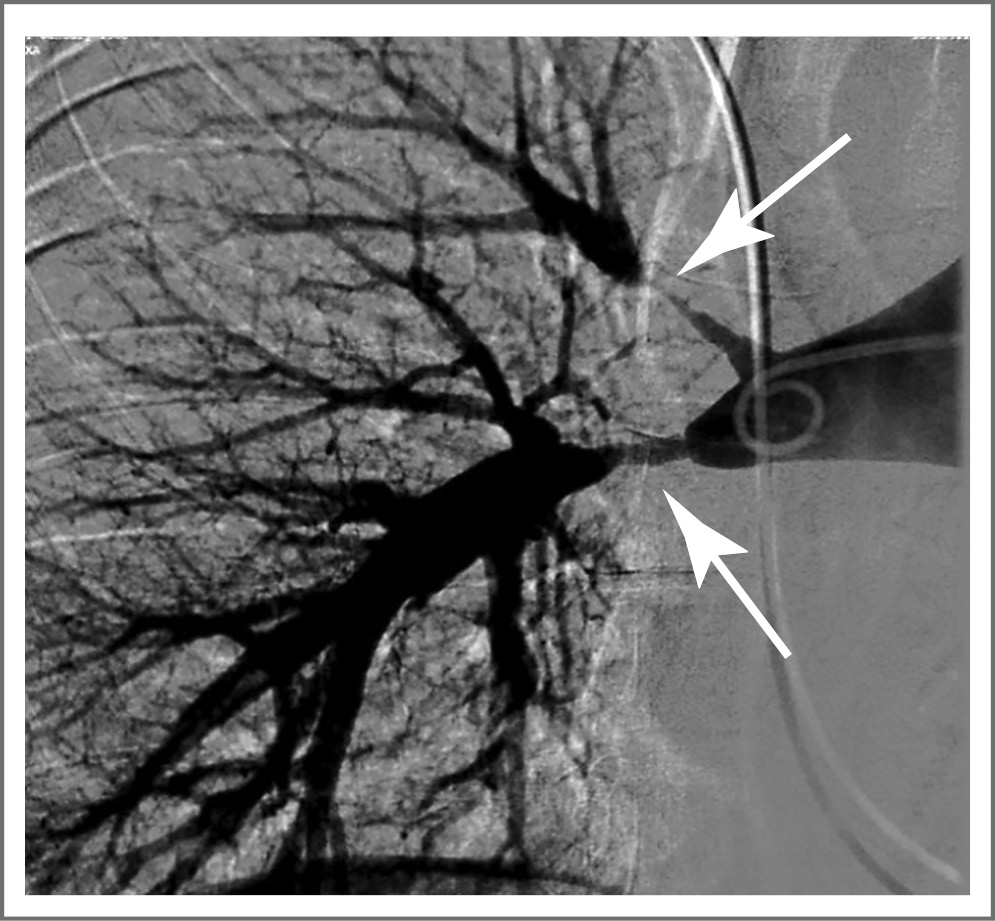

В последние годы все более широко используют магнитно-резонансную ангиографию и КТА [8, 76, 77]. Последняя является надежным неинвазивным инструментом выявления поражения как аорты, так и легочной артерии (рис. 1), в том числе на ранней стадии заболевания (до формирования стеноза), используется для ранней диагностики с возможностью мониторинга активности воспаления [78]. Показано, что для диагностики АТ чувствительность и специфичность КТА достигают 100% [79], при ГКА – 73 и 78% соответственно [72]. КТА с трехмерным изображением сосудов позволяет выявить изменения как просвета, так и стенки сосуда, но точность измерения толщины и плотности стенки значительно снижается за счет присутствия в сосудистом русле контраста. Кроме того, при КТА используют потенциально нефротоксичные контрастные вещества и присутствует лучевое воздействие, что существенно ограничивает возможности повторных исследований для динамического мониторинга.

Рис. 1. Селективная ангиопульмонография у пациентки с АТ: субтотальный стеноз в устьях и проксимальных сегментах верхнедолевой и нижнедолевой ветвей правой легочной артерии (стрелки).

Fig. 1. Selective angiopulmonography in a female patient with Takayasu's arteritis: subtotal stenosis at the orifices and proximal segments of the upper and lower lobe branches of the right pulmonary artery (arrows).